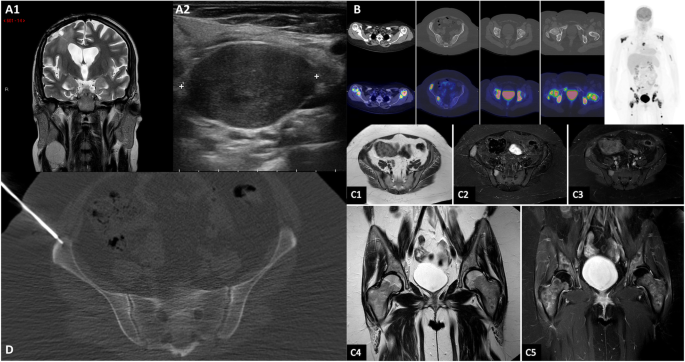

Fig. 3

Brain and pelvic MRI, Ultrasound, Whole body 18F-FDG PET/CT scan, CT guided biopsy. Legend: Coronal T2-wighted image shows the contemporary stability of the right frontal lesion (A1) with the appearance of a right cervical mass (A1, red arrow). Ultrasound in the right lateral cervical site confirms that the lymph node is increased in size (maximum diameter of 3.5 cm) with pathological structure (A2). Whole body 18F-FDG PET/CT scan shows multiple increased 18F-FDG uptake areas (B). None of them correlates with significant osteostructural alteration on CT scan. Pelvic MRI demonstrates focal signal alterations at sacrum and iliac wing on the right side on T1-weighted axial (C1), STIR (C2), T1 SPIR with Gd (C3), and diffuse signal alteration of both hips and proximal third of the femurs on T2-weighted coronal (C4) and T1 SPIR with Gd (C5). CT guided biopsy performed at the right iliac wing, based on PET images and MRI (D)

A 29-year-old healthy left-handed woman, admitted to another institution after the appearance of a focal motor epileptic seizure, underwent subtotal surgical removal of a right frontal WHO grade II Astrocytoma in June 2015 (Fig. 1, A1–2). The lesion remained stable at the following six-months follow-up MRI studies until October 2017, when the patient underwent a new brain surgery for neuroradiological findings of locoregional recurrence (Fig. 1, B1–2), without any clinical worsening. Histological investigations confirmed a WHO Grade II Astrocytoma (MGMT promoter methylated, IDH1-mutated; absence of 1p/19q deletion; ki-67 index: 4%; Fig. 2, A1–3). The Karnofsky Performance Status (KPS) score at discharge was 100. Five months after the second surgery the patient presented a sudden clinical worsening, with the appearance of left hemiparesis and focal motor epileptic seizures affecting the left upper limb. A new Brain MRI documented a massive recurrence of the right frontal lesion with evident signs of grading change (Fig. 1, C1–4). This motivated the third surgery performed in April 2018, which led to a subtotal resection. Histological investigations revealed a WHO grade IV (MGMT promoter methylated, IDH1-mutated; absence of 1p/19q deletion; ki-67 index: 60%; Fig. 2, B1–3). The patient was initially treated accordingly to the protocol recommended by Stupp et al. [5] with concomitant radiation therapy (2 Gy given five days per week for six weeks, total dose: 60 Gy) and chemotherapy with Temozolomide (75 mg/m2 per day for six weeks), followed by adjuvant chemotherapy with Temozolomide (200 mg/m2 for 5/28 days). Unfortunately, the adjuvant chemotherapy with Temozolomide was early suspended after two cycles because of grade III blood toxicity with pancytopenia. In September 2018, a right cervical lymph node swelling appeared. An ultrasound of the neck showed some lymph nodes increased in size (maximum diameter of 3.5 cm) with pathological structure in the right lateral cervical site (Fig. 3, A1–2). A needle biopsy was performed and, according to the immunohistochemical, biomolecular and histological results, confirmed the presence of an extracranial metastatic localization of GBM (Fig. 2, C1–3). A thoracic and abdominal CT scan ruled out further diffusion to other sites, and a brain MRI didn’t show any sign of progression of the primary lesion. Locoregional radiotherapy (6 Gy given for five consecutive fractions, total dose: 30 Gy), was performed leading to a complete remission of the 18F-FDG uptake in the right lateral cervical region at the five months follow-up. In addition, a second-line chemotherapy with Procarbazine-Lomustine was started, but it was stopped after the second cycle, because of grade III blood toxicity with pancytopenia. About two months after the last radiotherapy treatment, the patient complained of the appearance of severe diffuse drug resistant arthralgia and back pain, without any worsening at neurologic examination. A whole body 18F-FDG PET/CT scan showed multiple increased 18F-FDG uptake areas involving ilium bilaterally and the proximal third of the femurs (SUV max = 25), scapula and humeral head bilaterally (SUV max = 22), sternum (SUV max = 20), some ribs, some vertebrae and the sacrum (SUV max = 15; Fig. 3, B). None of the 18F-FDG uptake areas correlated with significant structural alteration on CT scan. Pelvis MRI demonstrated signal alteration areas compatible with GBM metastatic bone infiltration (Fig. 3, C1–5). Based on PET images and MRI, a CT guided biopsy was performed at the right iliac wing (Fig. 3, D) and the histopathological examination confirmed the presence of secondary bone localizations of GBM (Fig. 2, D1–3). In the face of this diffusion, brain-MRI documented stability of the brain disease for 14 months (Fig. 1, D1–4, E1–4; Fig. 3, A1) and no clinical or radiological signs of progression were discovered in the irradiated lymph node site for approximately 1-year. About 12 months after the appearance of the first metastatic site, the patient was hospitalized in a Hospice with a KPS score of 70 where died for extracranial progression of the disease and subsequent sepsis at the age of 33-years. Figure 4 summarizes the timeline of the patient’s history.